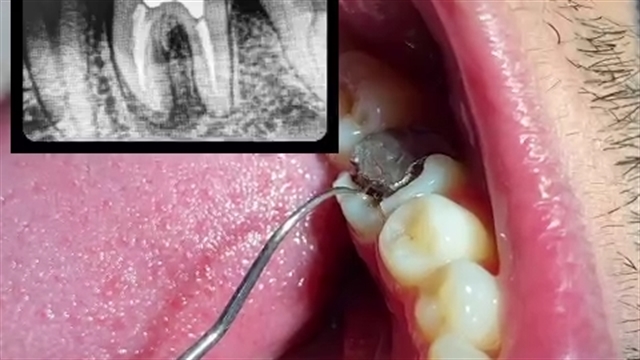

پخش صدا شکستگی تاج-ریشه دندان اشتراکگذاری لیست پخش ۰ نظر ۰ نظر دانلود دانلود ویدیو دانلود کیفیت 480p ۷۲۹.۲۶ کیلوبایت دانلود کیفیت 360p ۴۸۷.۲۴ کیلوبایت دانلود کیفیت 240p ۲۸۰.۸۵ کیلوبایت دانلود کیفیت 144p ۱۶۷.۳۴ کیلوبایت گزارش تخلف بیشتر گزینههای بیشتر لیست پخش لایکها گزارش تخلف ۰ لایک نغمه معراجی منتشر شده در تاریخ ۱۴۰۰/۰۸/۰۷ این کانال دنبال شد دنبال کردهاید دنبال کردن این کانال دنبال کردن ادامه نظرات لبخند لبخند لغو ثبت نظری برای نمایش وجود ندارد.